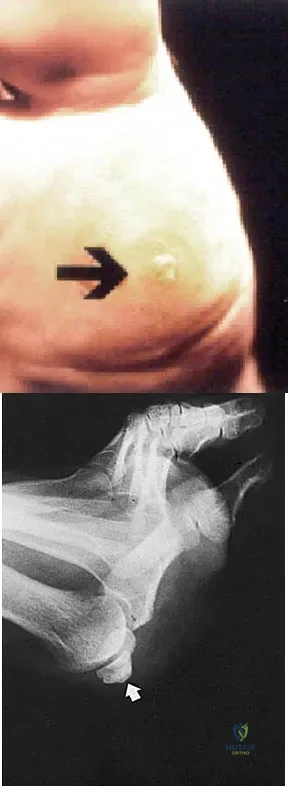

An obese 56-year-old woman with hypertension has had posterior heel pain for the past 6 months. She also notes some enlargement over the posterior aspect of the heel. Examination reproduces pain with palpation at the insertion of the Achilles tendon. A lateral radiograph is shown in Figure 45. What is the most likely diagnosis?

Figures 1a and 1b show the clinical photograph and oblique radiograph of a 52-year-old man who has plantar first metatarsal pain. A felt pad in the shoe proximal to the area of pain has failed to provide relief. Management should now consist of